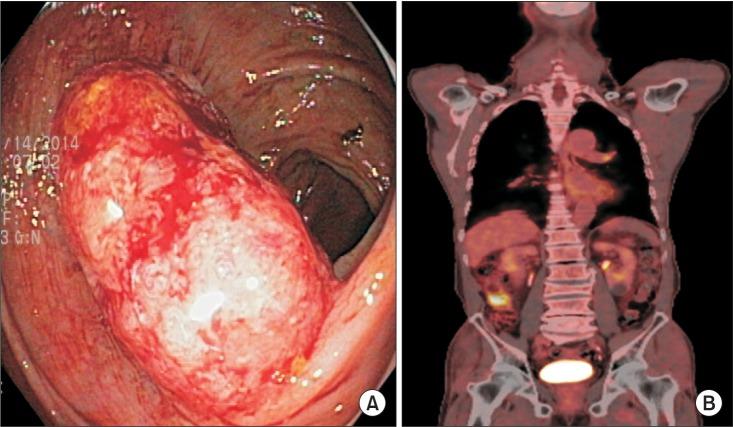

The concept of complete mesocolic excision and central vascular ligation for colonic cancer has been recently introduced. The paper describes a technique of right-sided complete mesocolic excision and intracorporeal anastomosis by using a single-port robotic approach with an additional conventional robotic port. We performed a single-port plus an additional port robotic surgery using the Da Vinci Single-Site platform via the Pfannenstiel incision and the wristed robotic instruments via an additional robotic port in the left lower quadrant. The total operative and docking times were 280 and 25 minutes, respectively. The total number of lymph nodes harvested was 36 and the proximal and distal resection margins were 31 and 50 cm, respectively. Single-port plus an additional port robotic surgery for right-sided complete mesocolic excision and intracorporeal anastomosis appears to be feasible and safe. This system can overcome certain limitations of the previous robotic systems and conventional single-port laparoscopic surgery.

结肠癌的完整结肠系膜切除和中央血管结扎概念最近已被引入。本文描述了一种通过使用单端口机器人方法并附加一个传统机器人端口进行右侧完整结肠系膜切除和体内吻合的技术。我们通过Pfannenstiel切口使用达芬奇单孔平台,并通过左下腹的一个附加机器人端口使用腕式机器人器械进行了单端口加一个附加端口的机器人手术。总手术时间和对接时间分别为280分钟和25分钟。总共收获了36个淋巴结,近端和远端切缘分别为31厘米和50厘米。用于右侧完整结肠系膜切除和体内吻合的单端口加一个附加端口机器人手术似乎是可行且安全的。该系统可以克服先前机器人系统和传统单端口腹腔镜手术的某些局限性。